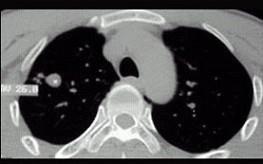

问题 男性,25岁,低热、咳嗽2月。胸部CT见图,最可能的诊断是 ( )

选项 A、肺脓肿 B、支气管扩张 C、肺结核球 D、肺癌 E、急性血行播散型肺结核

答案 C